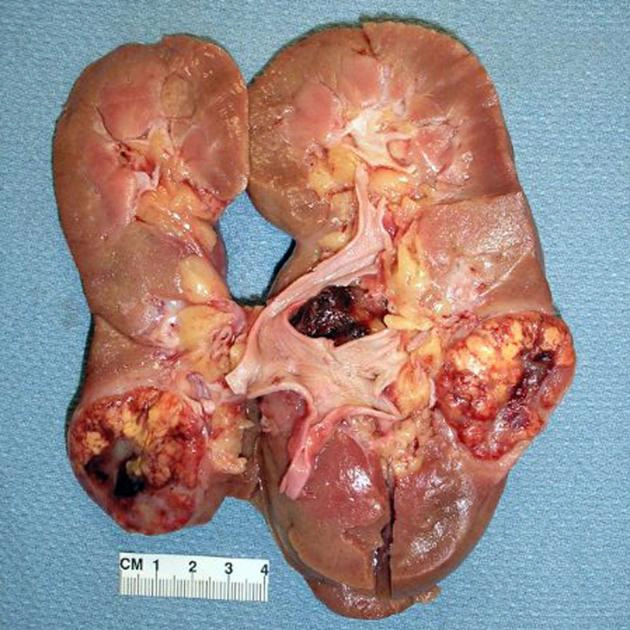

Ung thư biểu mô tế bào thận (Renal Cell Carcinoma - RCC)